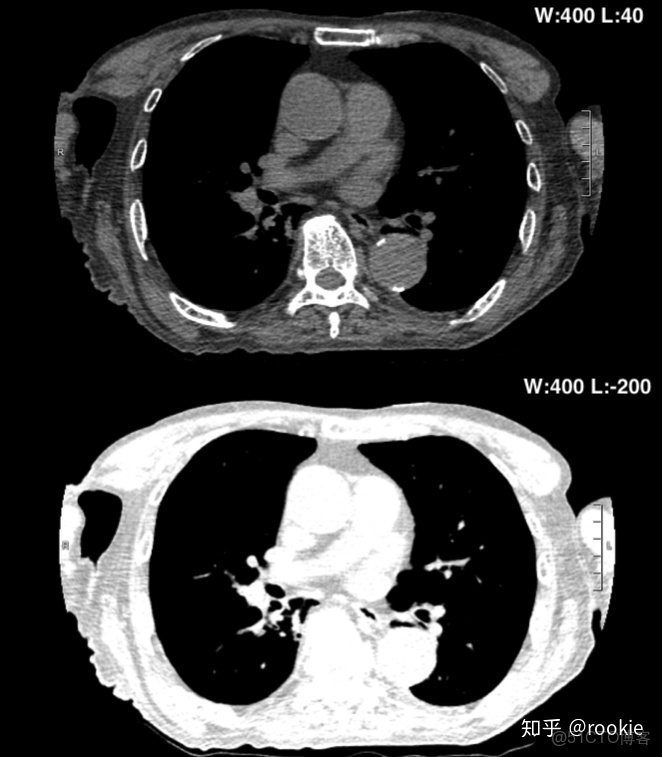

上面的圖像顯示了增加窗口寬度將如何降低圖像的對比度。與下窗格相比,頂部窗格的窗口寬度更小,皮下組織中的肌肉和脂肪之間的對比更加明顯。

調整窗位:增大窗位將降低圖像的亮度: 隨着窗口級別的增加,圖像將變得更暗。這是因為隨着級別的增加,將需要更高的HU值才能將密度表示為白色。減小窗位將增加圖像的亮度: 隨着窗口級別的增加,圖像將變得更暗。這是因為隨着水平的降低,需要較低的HU值才能將密度表示為白色。

CLAHE算法增強局部對比度的X光圖像增強效果對比_ico_07

上圖演示了降低窗口水平如何增加圖像亮度。頂部窗格具有更高的窗口水平,在窗口寬度內包含密度的組織比底部窗格中的組織要暗得多。